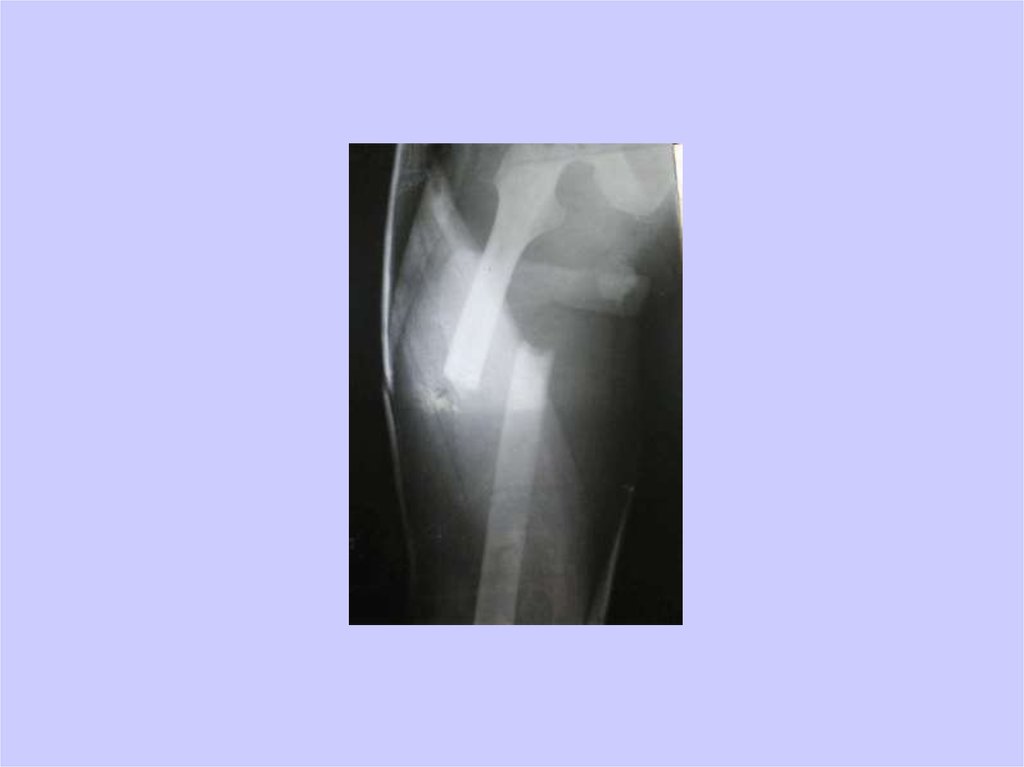

39. репозиция

40. И еще раз репозиция

41. И еще раз репозиция